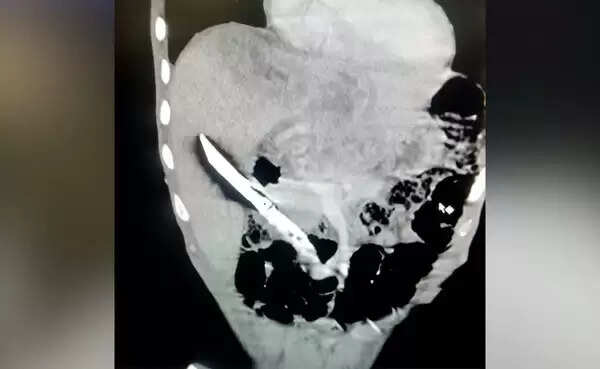

ന്യൂഡെല്‍ഹി: (www.kvartha.com 28.07.2020) കഞ്ചാവിന് അടിമയായ യുവാവ് ലഹരി കിട്ടാത്തതിനെ തുടര്‍ന്ന് വിഴുങ്ങിയത് കത്തി. ഹരിയാന സ്വദേശിയായ 28കാരനാണ് കത്തി വിഴുങ്ങിയത്. എന്നാല്‍ കത്തി വിഴുങ്ങിയ കാര്യം പുറത്തറിയിക്കാതിരുന്ന യുവാവ് ഒന്നരമാസത്തിനുശേഷം വയറുവേദന അനുഭവപ്പെട്ടതിനെ തുടര്‍ന്ന് ആശുപത്രിയില്‍ ചെന്ന് പരിശോധന നടത്തുകയായിരുന്നു. എക്‌സ്‌റേയില്‍ വയറ്റില്‍ കത്തി കണ്ടെത്തിയപ്പോഴാണു കുടുംബാംഗങ്ങള്‍ പോലും വിവരമറിയുന്നത്.

കത്തിയുമായി ഒന്നരമാസത്തിലേറെ ജീവിച്ച 28കാരനെ തുടര്‍ന്ന് ഓള്‍ ഇന്ത്യ ഇന്‍സ്റ്റിറ്റ്യൂട്ട് ഓഫ് മെഡിക്കല്‍ സയന്‍സസില്‍ പ്രവേശിച്ചു. അവിടെ വച്ച് ഏറെ സങ്കീര്‍ണമായ ശസ്ത്രക്രിയക്കു വിധേയനാക്കുകയും യുവാവിന്റെ കരളില്‍ നിന്ന് 20 സെന്റീമീറ്റര്‍ നീളമുള്ള കത്തി നീക്കം ചെയ്യുകയും ചെയ്തു. ഇയാളുടെ നില തൃപ്തികരമാണെന്ന് അധികൃതര്‍ പറഞ്ഞു.

അടുക്കളയിലും മറ്റും ഉപയോഗിക്കുന്ന ചെറുകത്തിയാണ് യുവാവ് വിഴുങ്ങിയത്. ശാരീരിക പ്രശ്‌നങ്ങളൊന്നും അനുഭവപ്പെടാത്തതിനാലാണ് വിവരം ആരോടും പറയാതിരുന്നതെന്ന് യുവാവ് പറയുന്നു.

കരളില്‍ തറച്ചിരുന്ന കത്തി എയിംസിലെ ഗ്യാസ്‌ട്രോ വിഭാഗം മേധാവി ഡോ.എന്‍ ആര്‍ ദാസിന്റെ നേതൃത്വത്തിലുള്ള സംഘമാണു നാലു മണിക്കൂര്‍ നീണ്ട ശസ്ത്രക്രിയയിലൂടെ പുറത്തെടുത്തത്. കത്തി വിഴുങ്ങിയ ആള്‍ക്കു ജീവന്‍ തിരികെ ലഭിച്ച ആദ്യ സംഭവമാകുമിതെന്നു ഡോക്ടര്‍മാര്‍ പറയുന്നു.

ഇതിനുമുമ്പ് ഇത്തരത്തിലുള്ള മൂന്നോ നാലോ കേസുകള്‍ കൈകാര്യം ചെയ്തിട്ടുണ്ട്. അത് സൂചി, പിന്‍, ഫിഷ് ഹുക്ക് എന്നിവ വിഴുങ്ങിയ കേസുകളാണ്. അതില്‍ നിന്നൊക്കെ വ്യത്യസ്തമായാണ് ഇത്രയും വലുപ്പമുള്ള കത്തി വിഴുങ്ങിയ സംഭവം ഉണ്ടായതെന്ന് ഡോക്ടര്‍മാര്‍ പറയുന്നു.